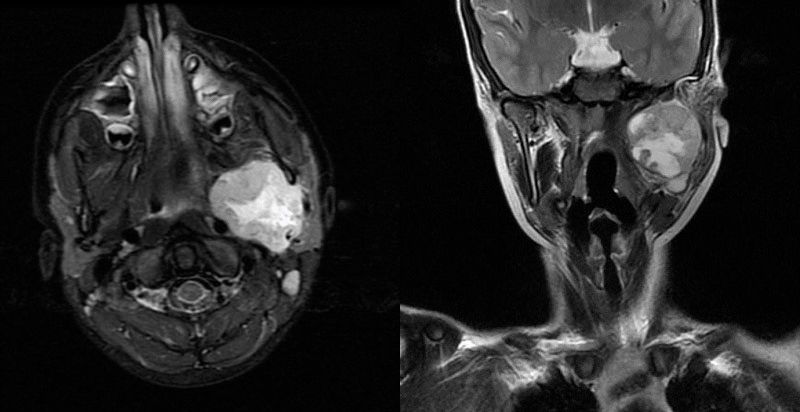

Se decide ingreso para estudio. Valorado por Otorrinolaringología, se objetiva parálisis de cuerda vocal derecha. Se realiza RM cerebral-cervical (Fig. 1), en la que se aprecia una masa polilobulada, que afecta a los espacios parafaríngeo, parotídeo y masetero izquierdos, de 42x40x48 mm, impresionando de naturaleza tumoral. Inicia corticoterapia, con mejoría de la cefalea, y se completa estudio de extensión, descartando afectación sistémica. Se comenta en sesión multicisciplinar con el Comité de Tumores Pediátricos, donde se decide intervención quirúrgica con fines diagnósticos-terapéuticos: se realiza resección quirúrgica completa (estadiaje posquirúrgico IRS I). No afectación de ganglios linfáticos (N0).

Figura 1. RM cerebral-cervical. Plano coronal y transversal.